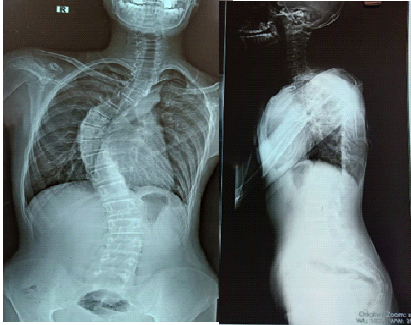

A 17-year-old boy visited the Spine OPD at Sanjay Gandhi Institute of Trauma and Orthopedics, Bangalore, with the complaints of back pain and progressive deformity for 4 years (Fig. 1). On clinical examination and X-rays, the patient had right sided thoracic scoliosis with no neurological deficits (Fig. 2).

Figure 2: X-ray showing scoliosis with the right main thoracic curve.